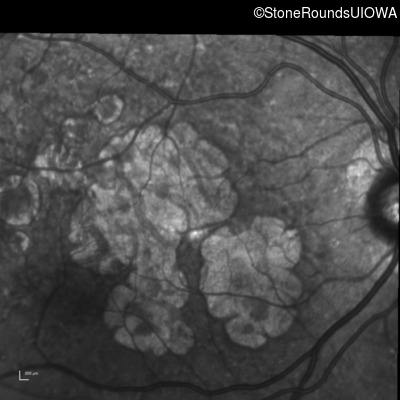

Blue Autofluorescence - Right - 20/25

Exemplar